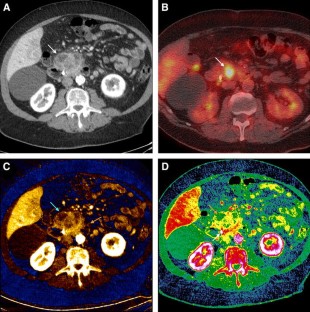

Fig. 1